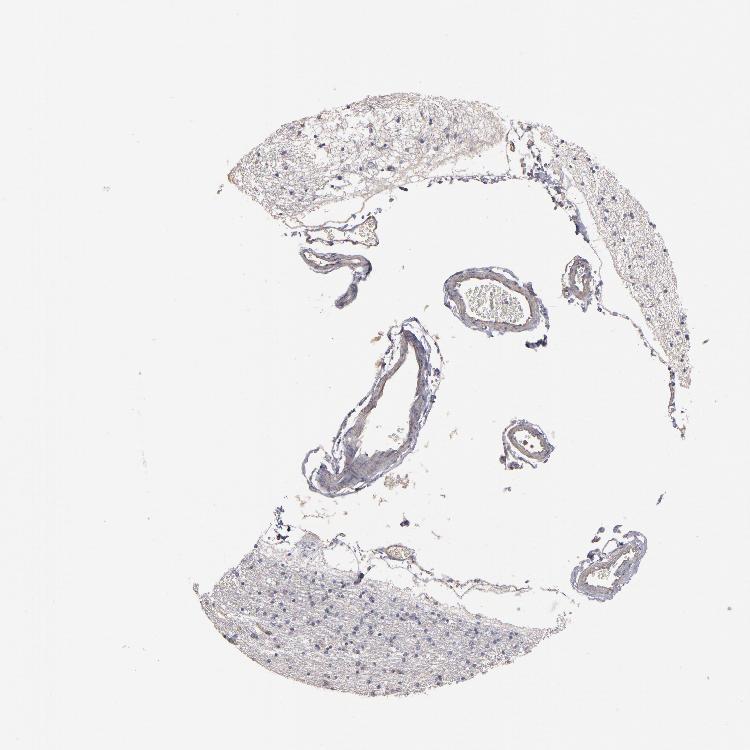

HIPPOCAMPUS - Antibody stainingi

Antibody staining in the annotated cell types in the current human tissue is reported as not detected, low, medium, or high, based on conventional immunohistochemistry profiling in selected tissues. This score is based on the combination of the staining intensity and fraction of stained cells.

Each image is clickable and will lead to virtual microscopy that enables deeper exploration of all samples and also displays staining intensity scores, fraction scores and subcellular localization as well as patient and tissue information for each sample.

Antibody HPA002132

Glial cells Low

Neuronal cells Low